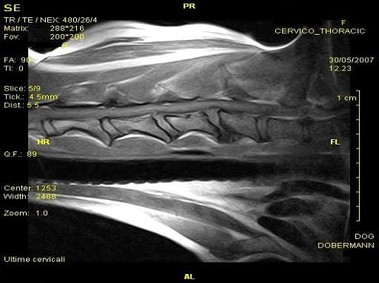

В настоящее время МРТ является наиболее предпочтительным методом визуализации любых мягких тканей, особенно для визуализации травм и патологий центральной нервной системы и суставов. Особенности Vet-MR позволяют использовать данный метод визуализации также в сфере ветеринарии.

Vet-MR специально разработана для визуализации небольших животных и является результатом внимания к деталям при разработке магнита, катушки и электронных компонентов, обеспечивая высокое качество экономически эффективной и простой в использовании МРТ в сфере ветеринарии.

- Высокое качество изображения